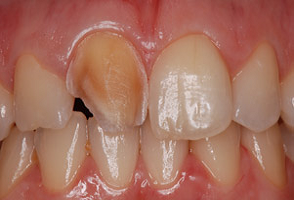

Cas 3 : Couronne toute céramique sur inlay-core céramisé et facette céramique sur deux incisives centrales chez un homme

La réalisation concomitante avec la même céramique usinée sur deux incisives centrales supérieures d’une couronne céramique sur dent dépulpée et d’une facette sur dent vivante permet d’optimiser le rendu esthétique du sourire